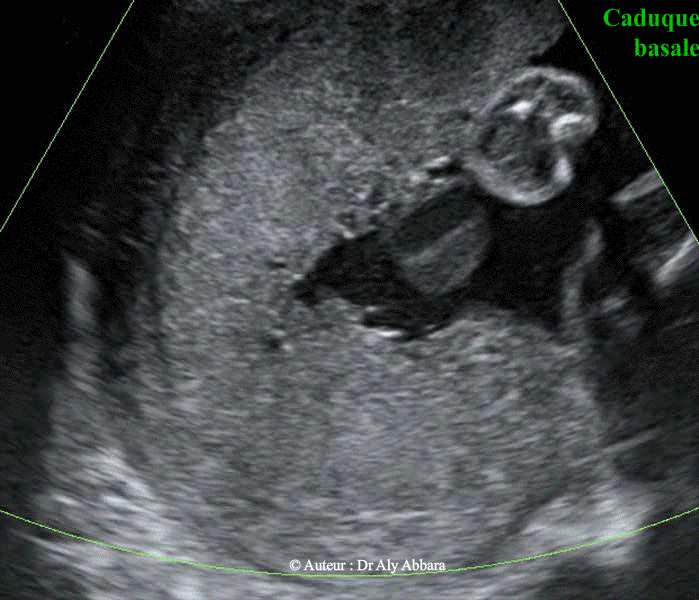

• Images échographiques par voie transpariétale abdominale mettant en évidence l’aspect habituel et normal de la zone de l'insertion du placenta sur la paroi de l'utérus :

Sur une coupe parfaitement sagittale (plan vertical, perpendiculaire au plan vu de face de la paroi utérine et du placenta) on peut distinguer trois couches distinctes :

• I- La paroi de l'utérus (le myomètre)

II- Le placenta

• II- Puis entre le myomètre et le placenta on peut observer la présence d'un liseré hypo-an-échogène séparant le myomètre du placenta ; ce liseré correspond anatomiquement à la caduque basale et son riche réseau veineux qui constituent le plan de clivage physiologique du placenta lors de la délivrance.

Un des signes évoquant le diagnostic de " placenta accreta " est la disparition de ce liseré, car cela témoigne de la disparition de la caduque basale et l'insertion directe des villosités trophoblastiques sur le myomètre (un organe juxtaposé en particulier la vessie quand il s'agit de placenta praevia antérieur percreta).

Les images publiées dans cette page ont été réalisées chez une femme enceinte de 28 semaines d'aménorrhée.